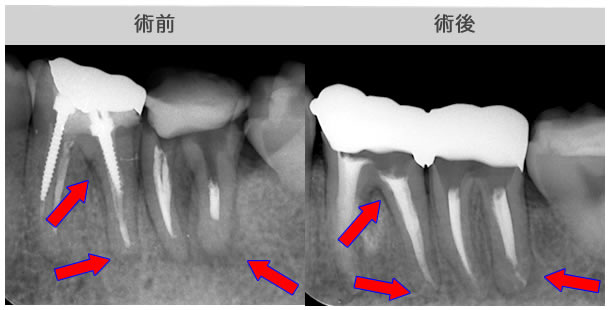

| 治療説明 | 右下第2小臼歯、他院で根管治療した後に頬側根尖部から排膿があます。X線CT画像では、根管が2本あり、そのうち舌側が根管充填されていませんでした。顕微鏡下で2根管とも根管充填処置を行い、4ヶ月で、X線透過像は消失しました。 |

|---|---|

| 治療期間 | 6〜24ヶ月 |

| 治療費用 | 150,000〜300,000円 |

| 治療に伴うリスク | 根管内からの治療で根尖病巣が治らない場合は、外科的に根尖病巣を除去する必要があります。 再根管治療を繰り返す場合、歯根の厚みが薄くなり、歯根破折のリスクが高まります。 |

| 治療説明 | クラウン・メタルコアを除去し、前医が根充した根充剤を除去、根尖まで穿通したことを確認後、根管充填を行いました。1ヶ月後には症状は消退しました。 |

|---|---|

| 治療場所 | 左側第一大臼歯 |

| 主訴 | 根尖部違和感・噛んだ時に痛む |

| 治療期間 | 6〜24ヶ月 |

| 治療費用 | 150,000〜300,000円 |

| 治療に伴うリスク | 根管内からの治療で根尖病巣が治らない場合は、外科的に根尖病巣を除去する必要があります。 再根管治療を繰り返す場合、歯根の厚みが薄くなり、歯根破折のリスクが高まります。 |

| 治療説明 | 右上第一大臼歯、夜間に急激に痛み受診されました。前医では治療困難で抜歯を勧められた患者さまです。X線画像では、頬側2根の根尖部X線透過像があり、修復物を除去すると根管内から排膿がありました。根管内洗浄、拡大清掃、排膿が無くなった後に根管充填処置3ヶ月後には、X線画像上でもX線透過像は消失していました。 |

|---|---|

| 治療場所 | 右上大臼歯 |

| 主訴 | 根尖部の透過像のため他院で抜歯を勧められた |

| 治療期間 | 6〜24ヶ月 |

| 治療費用 | 150,000〜300,000円 |

| 治療に伴うリスク | 根管内からの治療で根尖病巣が治らない場合は、外科的に根尖病巣を除去する必要があります。 再根管治療を繰り返す場合、歯根の厚みが薄くなり、歯根破折のリスクが高まります。 移植した自家骨または、人工骨が歯肉の縫合の裂開により感染することがあります。 |